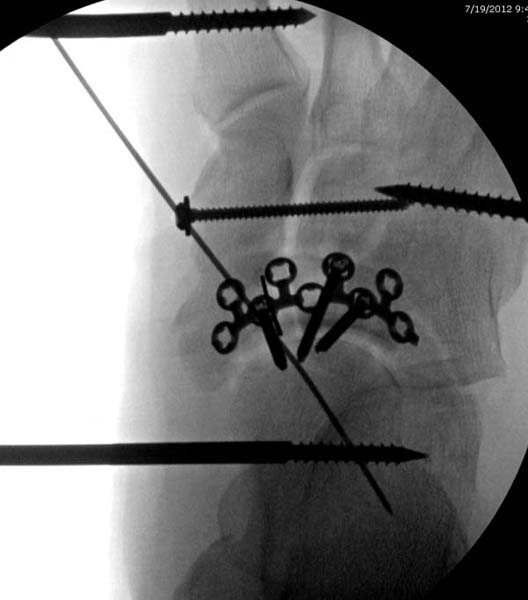

Через три дня повторная I&D, где через рану манипулировали дистальным фрагментом с установкой пары межфрагментарных шурупов. На рану вакуум и следующая обработка закончилась закрытием раны. Отек держался немного дольше, чем обычно.

После спадения отека вариантов фиксации много, включая мининвазивную технику, но данный случай закончили установкой простого аппарата Илизарова.

Через три дня оперирована стопа и для нейтрализации сил колонн оставили наружный фиксатор.